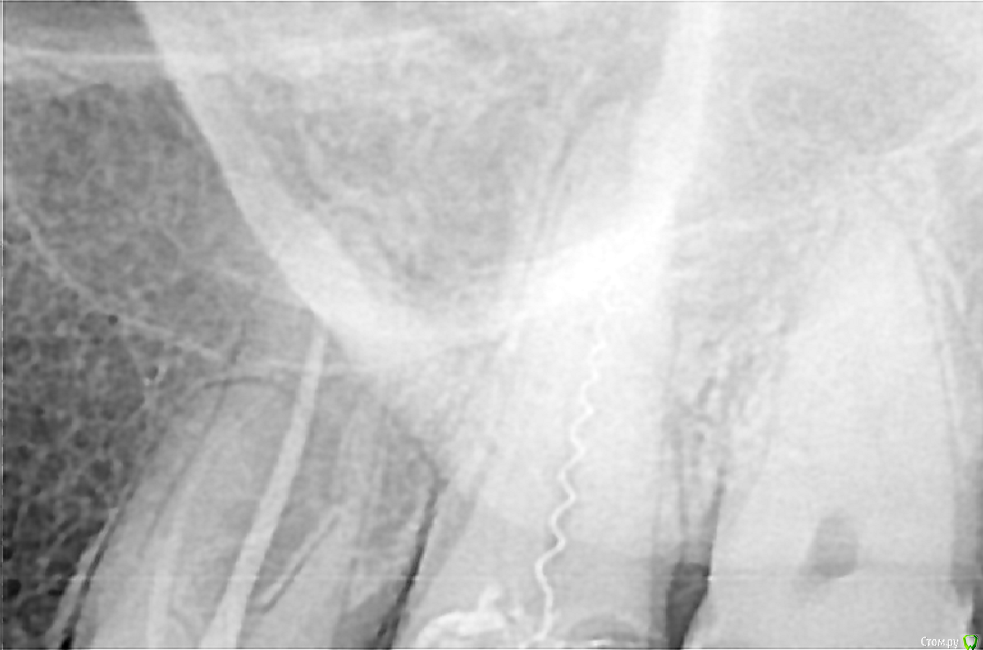

Закон парных случаев в этот летний месяц превзошел себя! Апогеем стал периодонтит 34 с двумя каналонаполнителями, при этом один торчал за апекс. Тут пришлось повозиться, достал через 40 минут. И вроде бы апикальный упор был и мерял-перемерял и всё равно паф.((( Как думаете мастер за апексом? Так как дело было летом, после НГ вызову на контроль и обязательно поделюсь результатом!